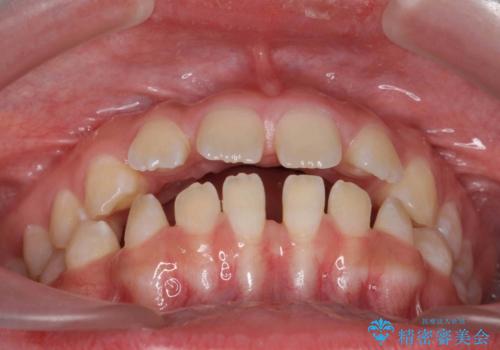

隙間を閉じる際、奥歯が倒れたため、途中ワイヤー矯正を併用しています。

上の前歯の隙間を閉じながら前歯を後方に下げているため、口元もひっこみ、口が閉じやすくなりました。